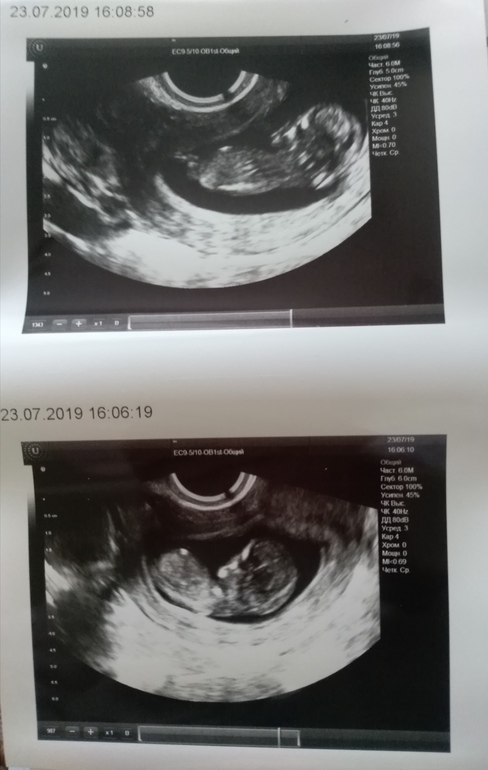

Приложу снимки, может кто своим опытным взглядом увидит, кто же там в домике живёт?

Предположила мальчика, но сказала не совсем понятно) молодая доктор совсем, думаю дай ещё тут спрошу :)